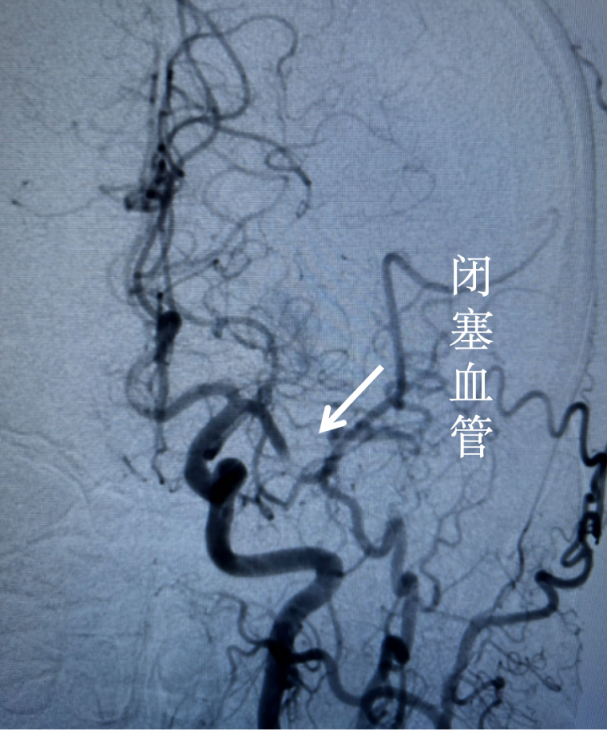

情况紧急,郭宝立刻打电话汇报科主任,并上报总值班,指示一切以患者为主,紧急救治病人。手术台上,急诊造影发现左侧大脑中动脉闭塞。造影结束,患者家属陆续赶到并补签字。

手术非常顺利,不到1小时血管开通,血栓取出。术后,患者即刻可以说话,肢体可以抬起。患者流着眼泪看着郭宝,好像有很多话要说,但只说出来两个字,“谢谢!”这一刻,所有的努力都值得。